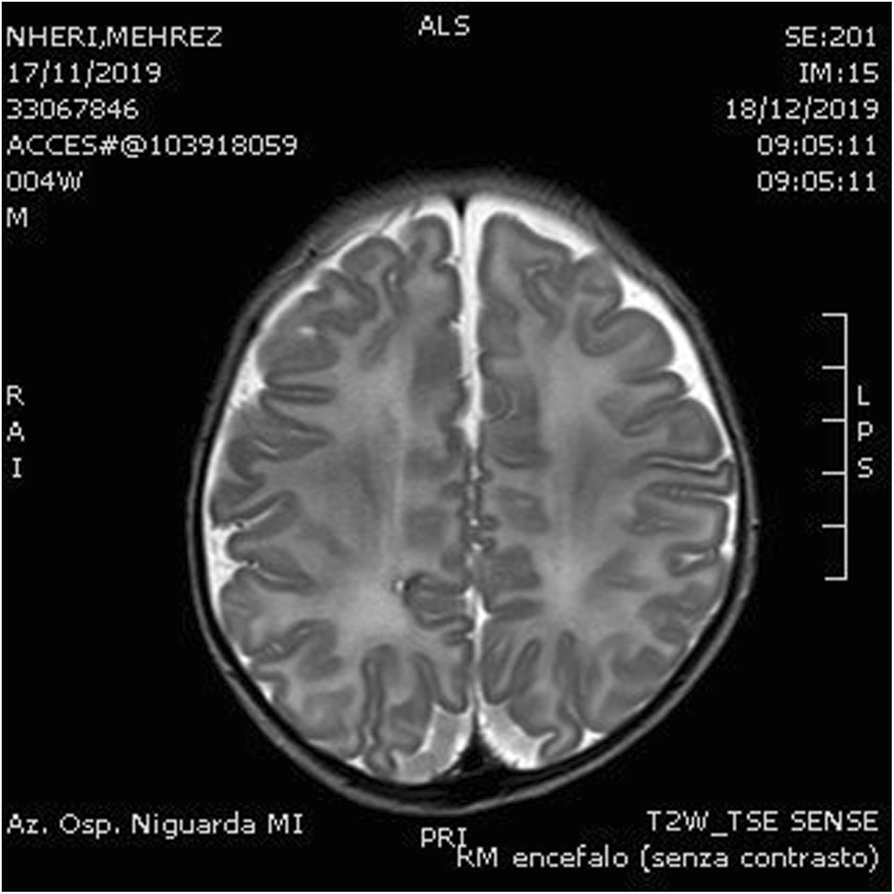

Fig.2 (abstract A19).From: Proceedings of the 33rd Congress of the Italian Society of Neonatology, Lombardy Section, 31 January - 1 February 2020T2 RMN on day 30Back to article page